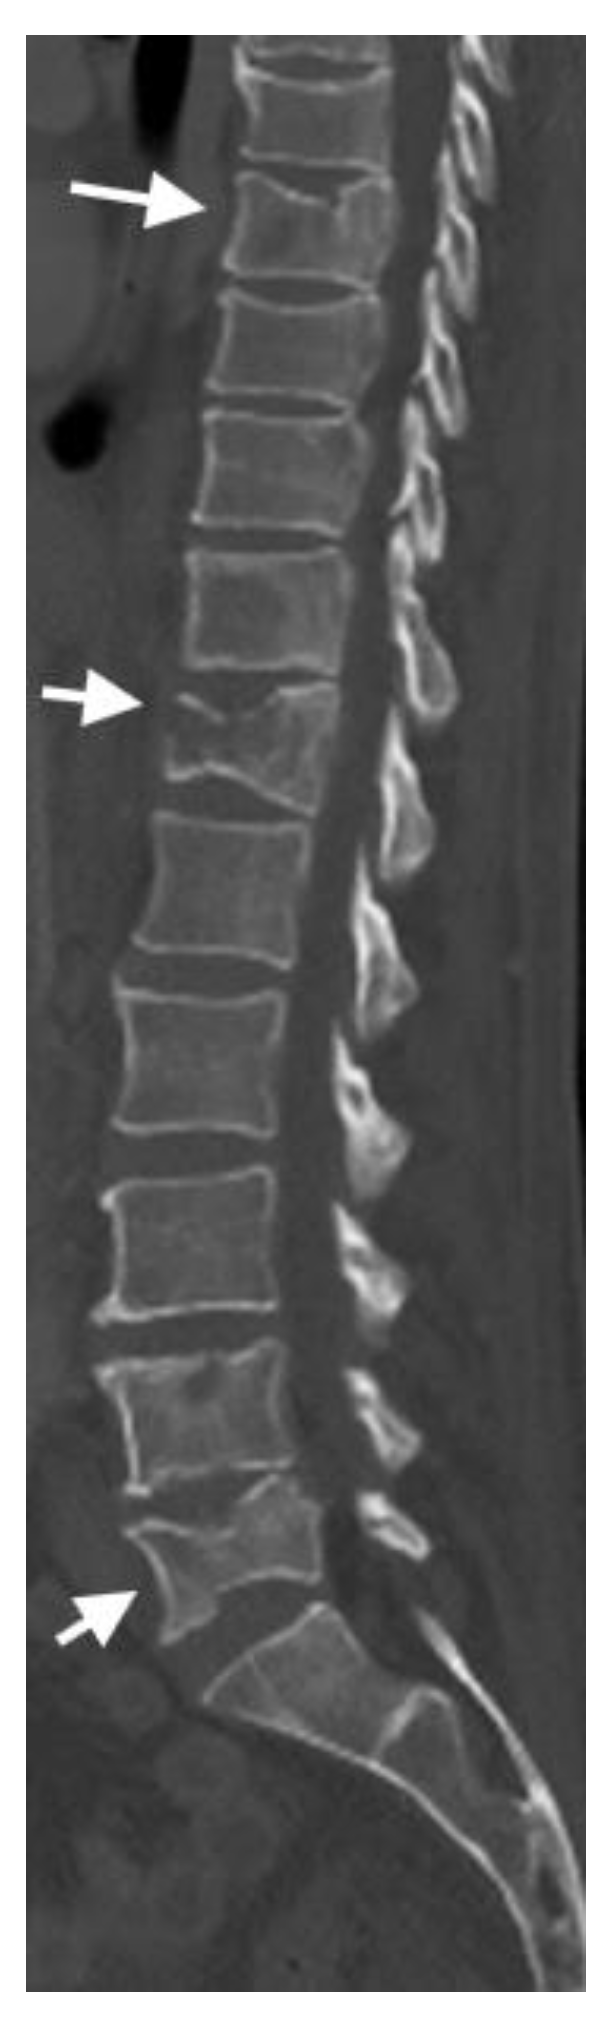

4.2. CT Scans

| CT including DECT | Detailed cross-sectional images of bone and vertebral structures |